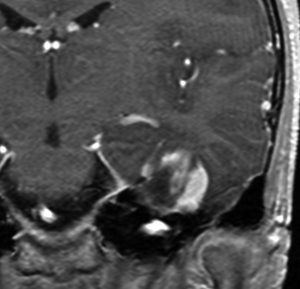

60代の女性に無症候で発見された稀な部位のPXA。結節様ですが脳とのはっきりした境はなく,多房性ののう胞を伴っていました。T2とFLAIR像ではわずかな浸潤像あるいは腫瘍周辺浮腫が疑われます。PXAに特徴的な画像ですが,大脳深部発生でもあり,PXAと画像診断することはできません。定位脳生検術 MRI-guided sterotactic biopsyで病理組織診断を行ない経過観察しました。

3年観察したら嚢胞を伴って増大しました。幸いのう胞性拡大が脳表方向であったのでparietal transcortical approachで全摘出できました。側脳室三角部腫瘍への到達法と同じアプローチですが,この経路では頭頂葉症候を後遺することがありません。

術後は無症状で8年間再発はありません。